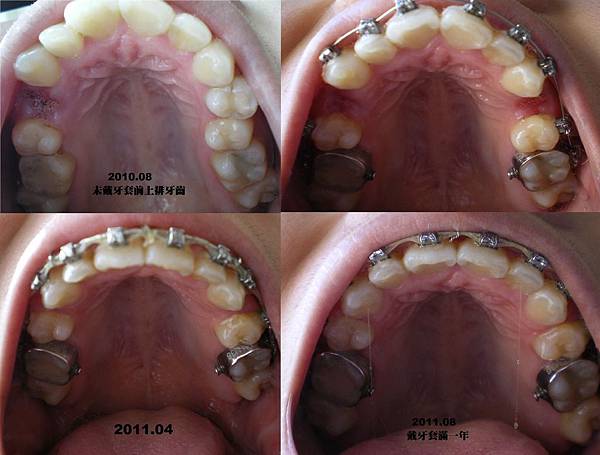

上次發表完臉型大變化之後,把這一年來拍的照片整理一下做個回顧展。

但是我沒有很勤勞的拍照,加上照相機的時間設定有誤,有些照片的時間都亂掉。

所以我盡可能的整理出來前後的差異。

首先,先來看上排牙齒的變化。